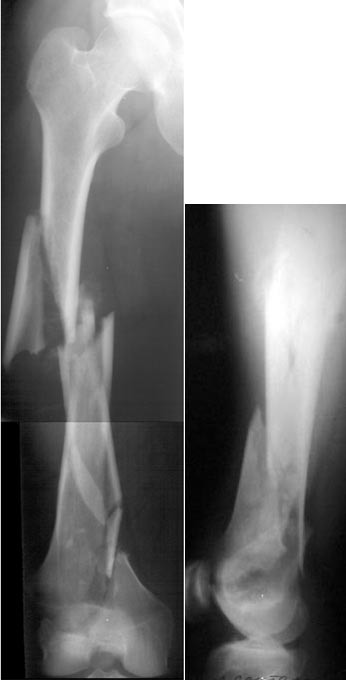

Мы пошли на операцию с планом попытаться сделать закрытый интрамедулярный, а не получится - сделать аппаратом. Посчитали, что получилось, хотя на еженедельной конференции ожидаются некоторые проблемы с объяснениями ;-)

Насчет стабильности для ранней нагрузки, конечно, сомнительно, но при таком повреждении ранняя нагрузка противопоказана в любом случае. Для ранних движений Должно хватить. Снимки в следующем сообщении.

Since it was done closed the shaft will heal or at worst need an exchange IMN.

Nice job.